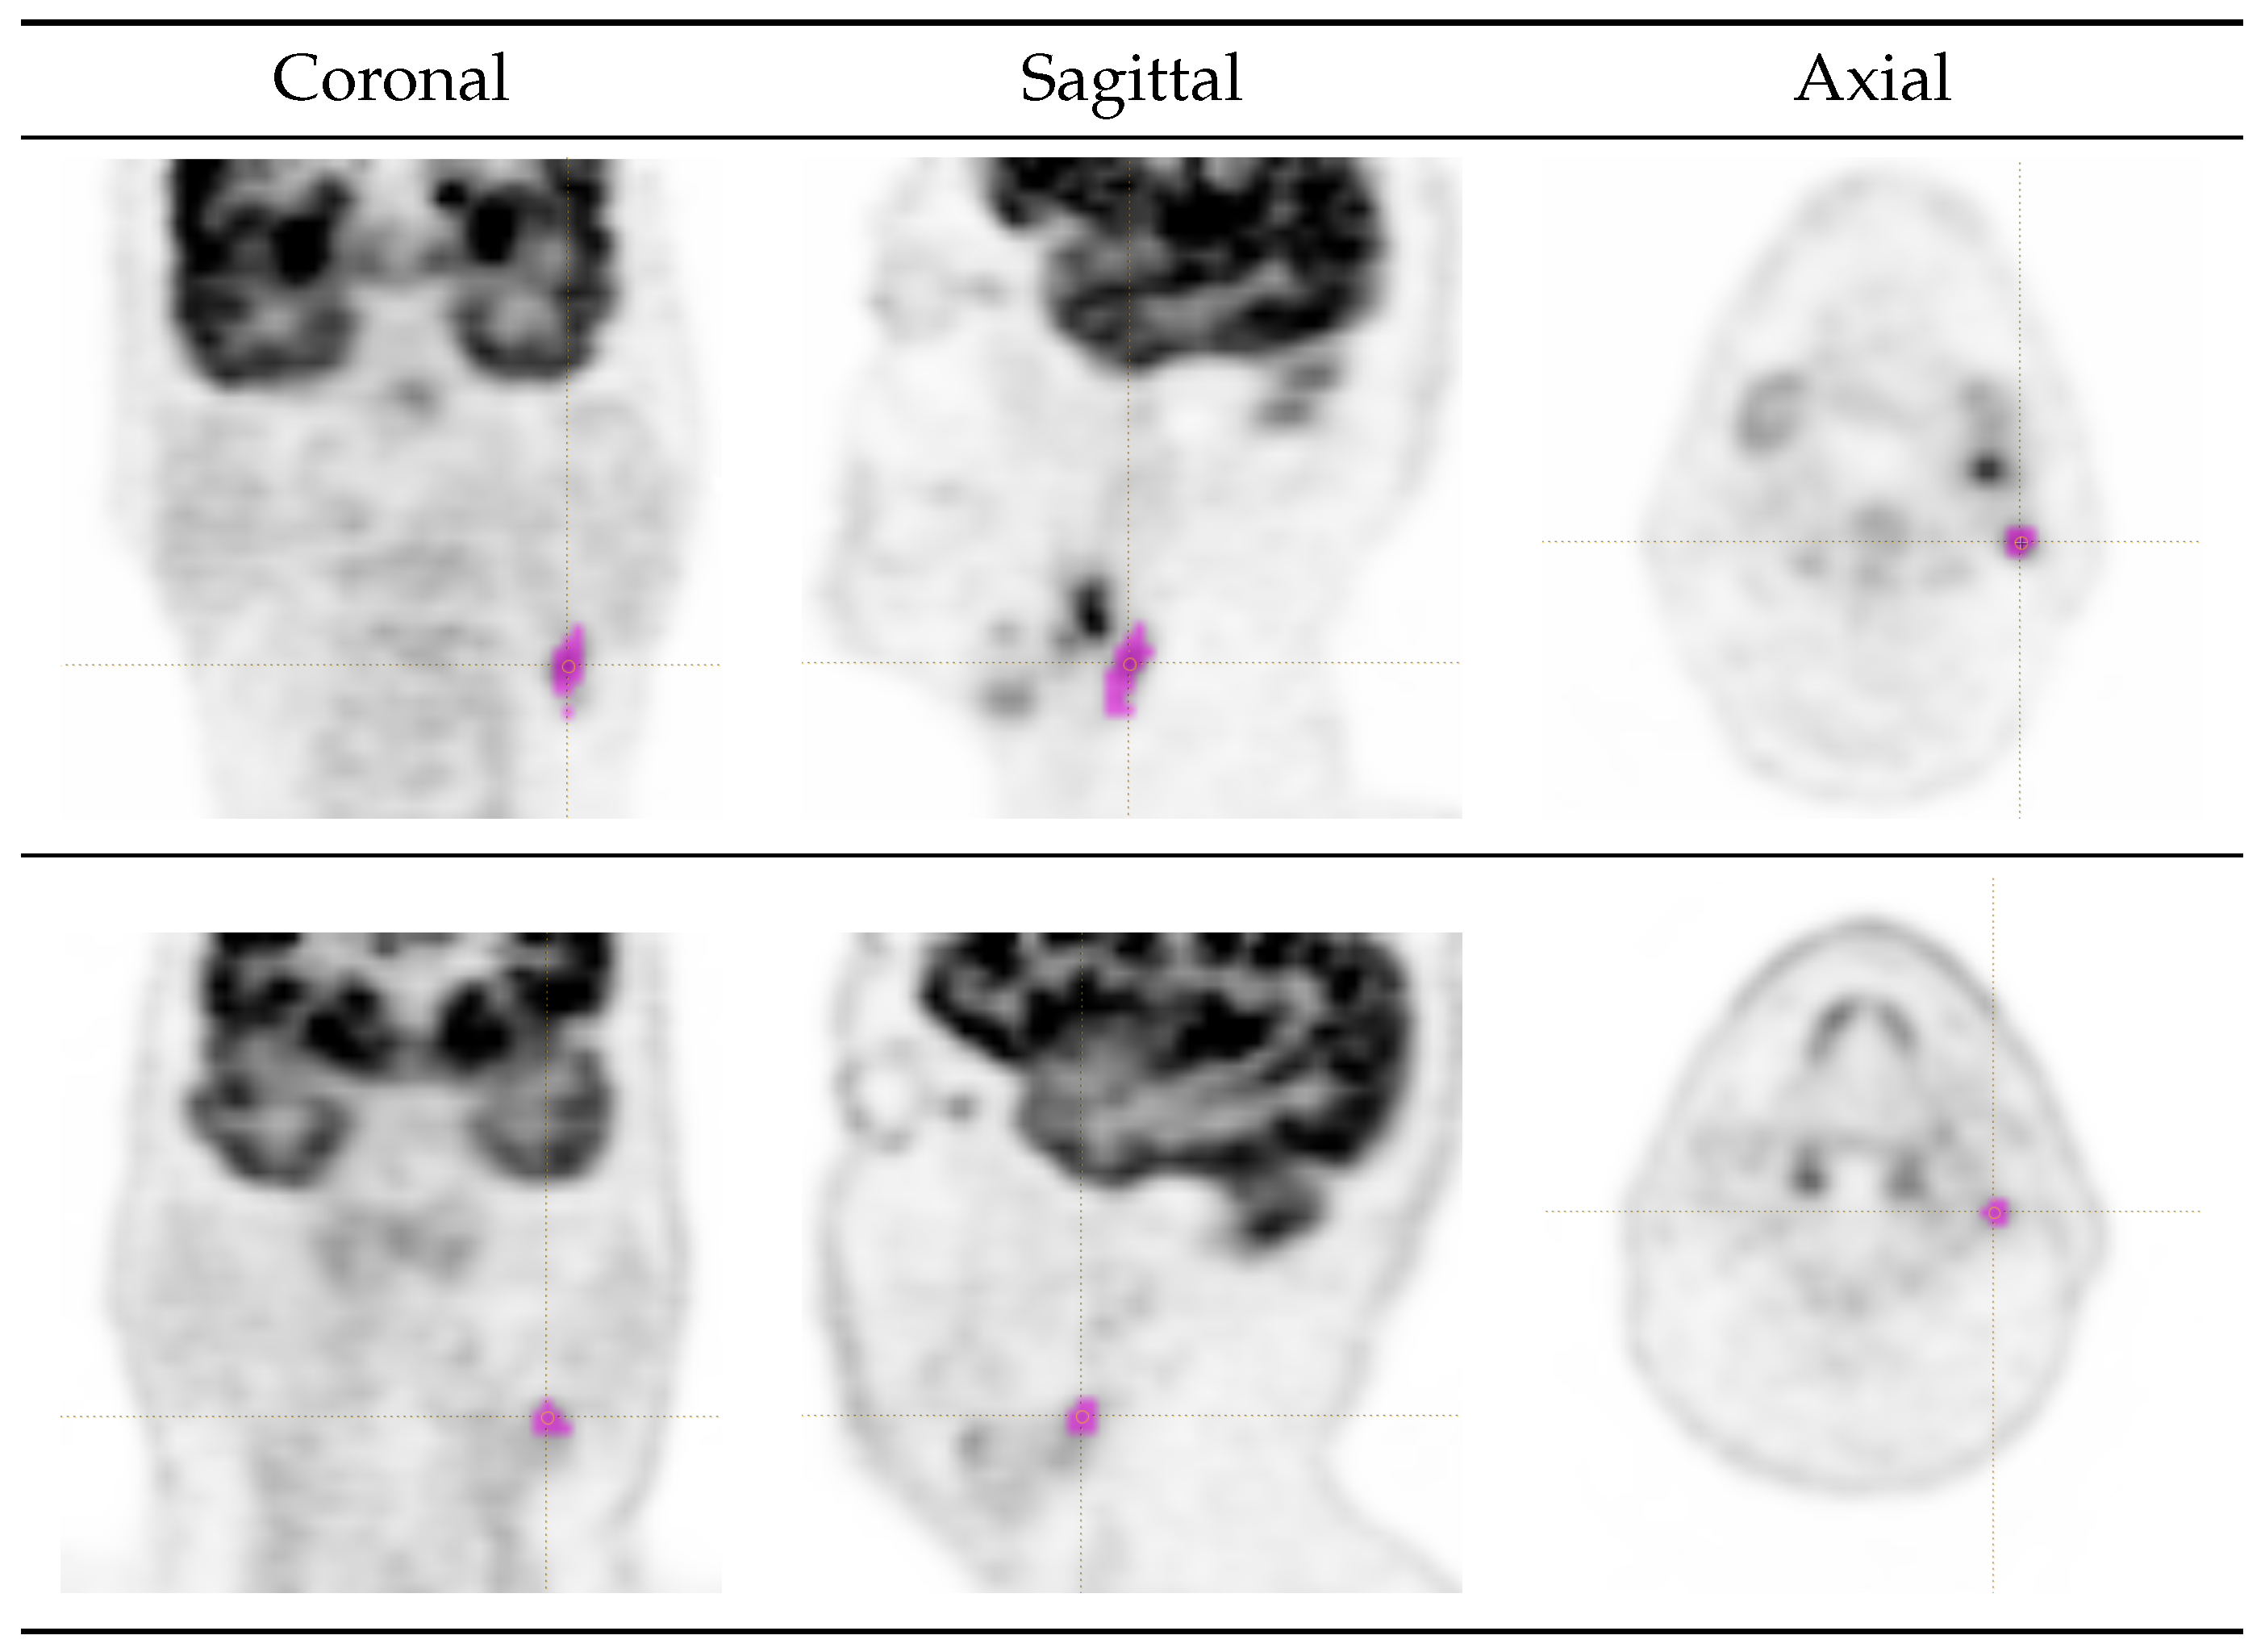

2.3. Lesion Delineation